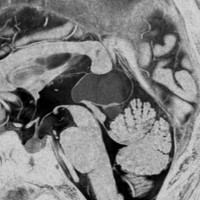

中年の男性に発生した中間型松果体実質腫瘍 グレード2です。水頭症(脳室の拡大)がみられます。水頭症のために頭痛と嘔吐で発症しました。開頭手術で全摘出してから,46グレイの腫瘍局所への放射線治療をしました。治療後10年経ちますが再発していません。